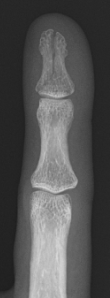

トモシンセシスはX線管の角度を変えながら撮影を行い、得られた複数の投影X線画像から任意高さの断層像を得る手法です。

単純撮影に比べ微細な骨折の描出に優れます。

データご提供:日本鋼管病院様